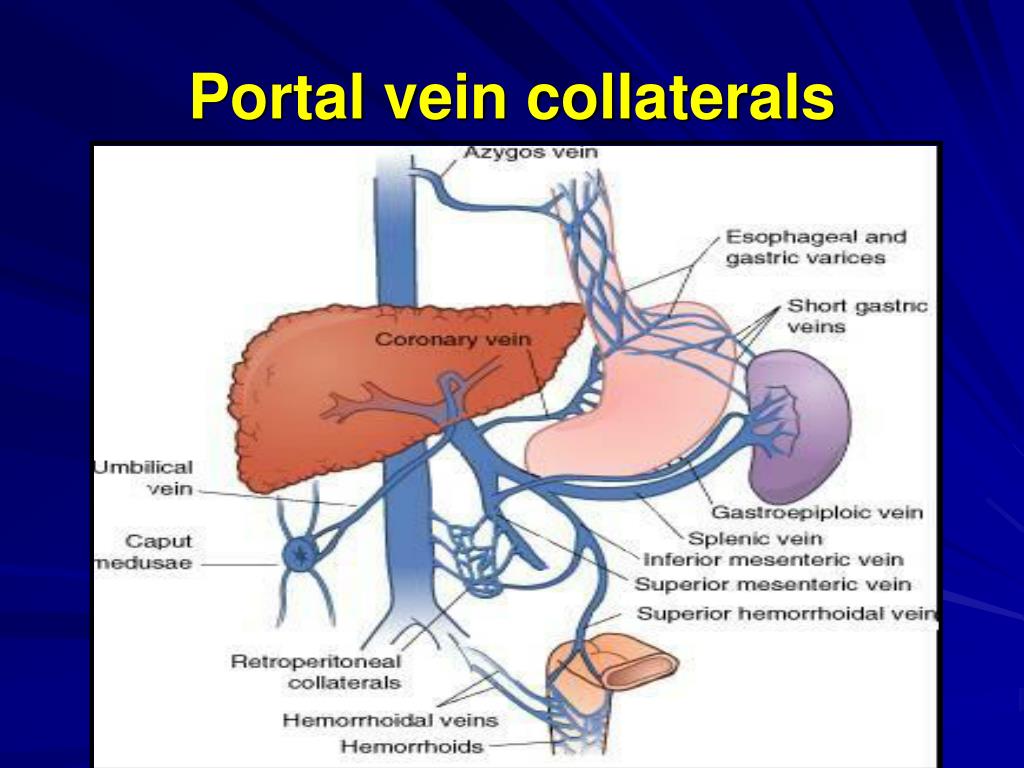

Portal Venous Collaterals